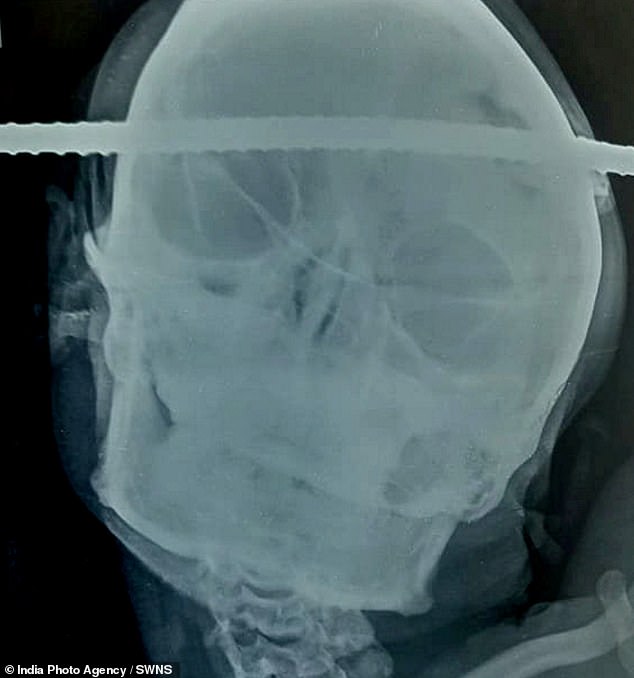

El joven de Balaghat, en el centro de la India, fue llevado al hospital BJ en las cercanías de Gondia, después de que la barra de hierro atravesara la región temporal derecha de su cerebro hasta la región frontal izquierda.

Milagrosamente, después de una hora y media de cirugía, la varilla se retiró de manera segura sin apenas sangrado o lesión en el área circundante.